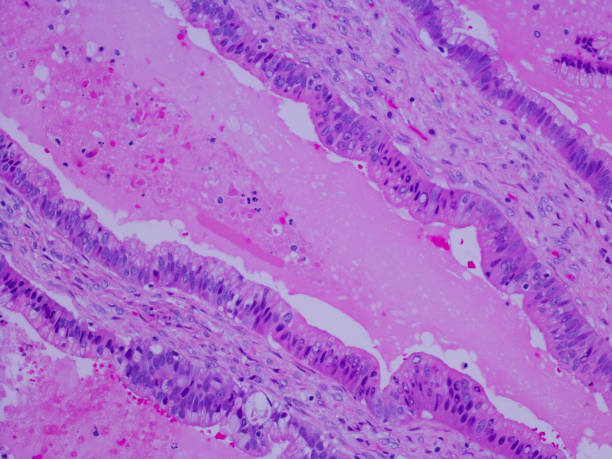

췌장암 초기증상 5. 췌장염

췌장암 초기증상 열 번째는 췌장염인데요. 췌장염은 췌장암으로 이어질 수 있어요. 이것은 만성 췌장염과 급성 췌장염 모두에 적용돼요. 특히나 만성 췌장염이 있다면 정기적인 췌장암 검진을 받는 것이 좋아요.